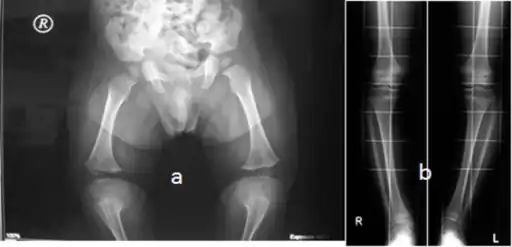

a,b)10 year old with hypochondroplasia (with variable degrees of genu varum)